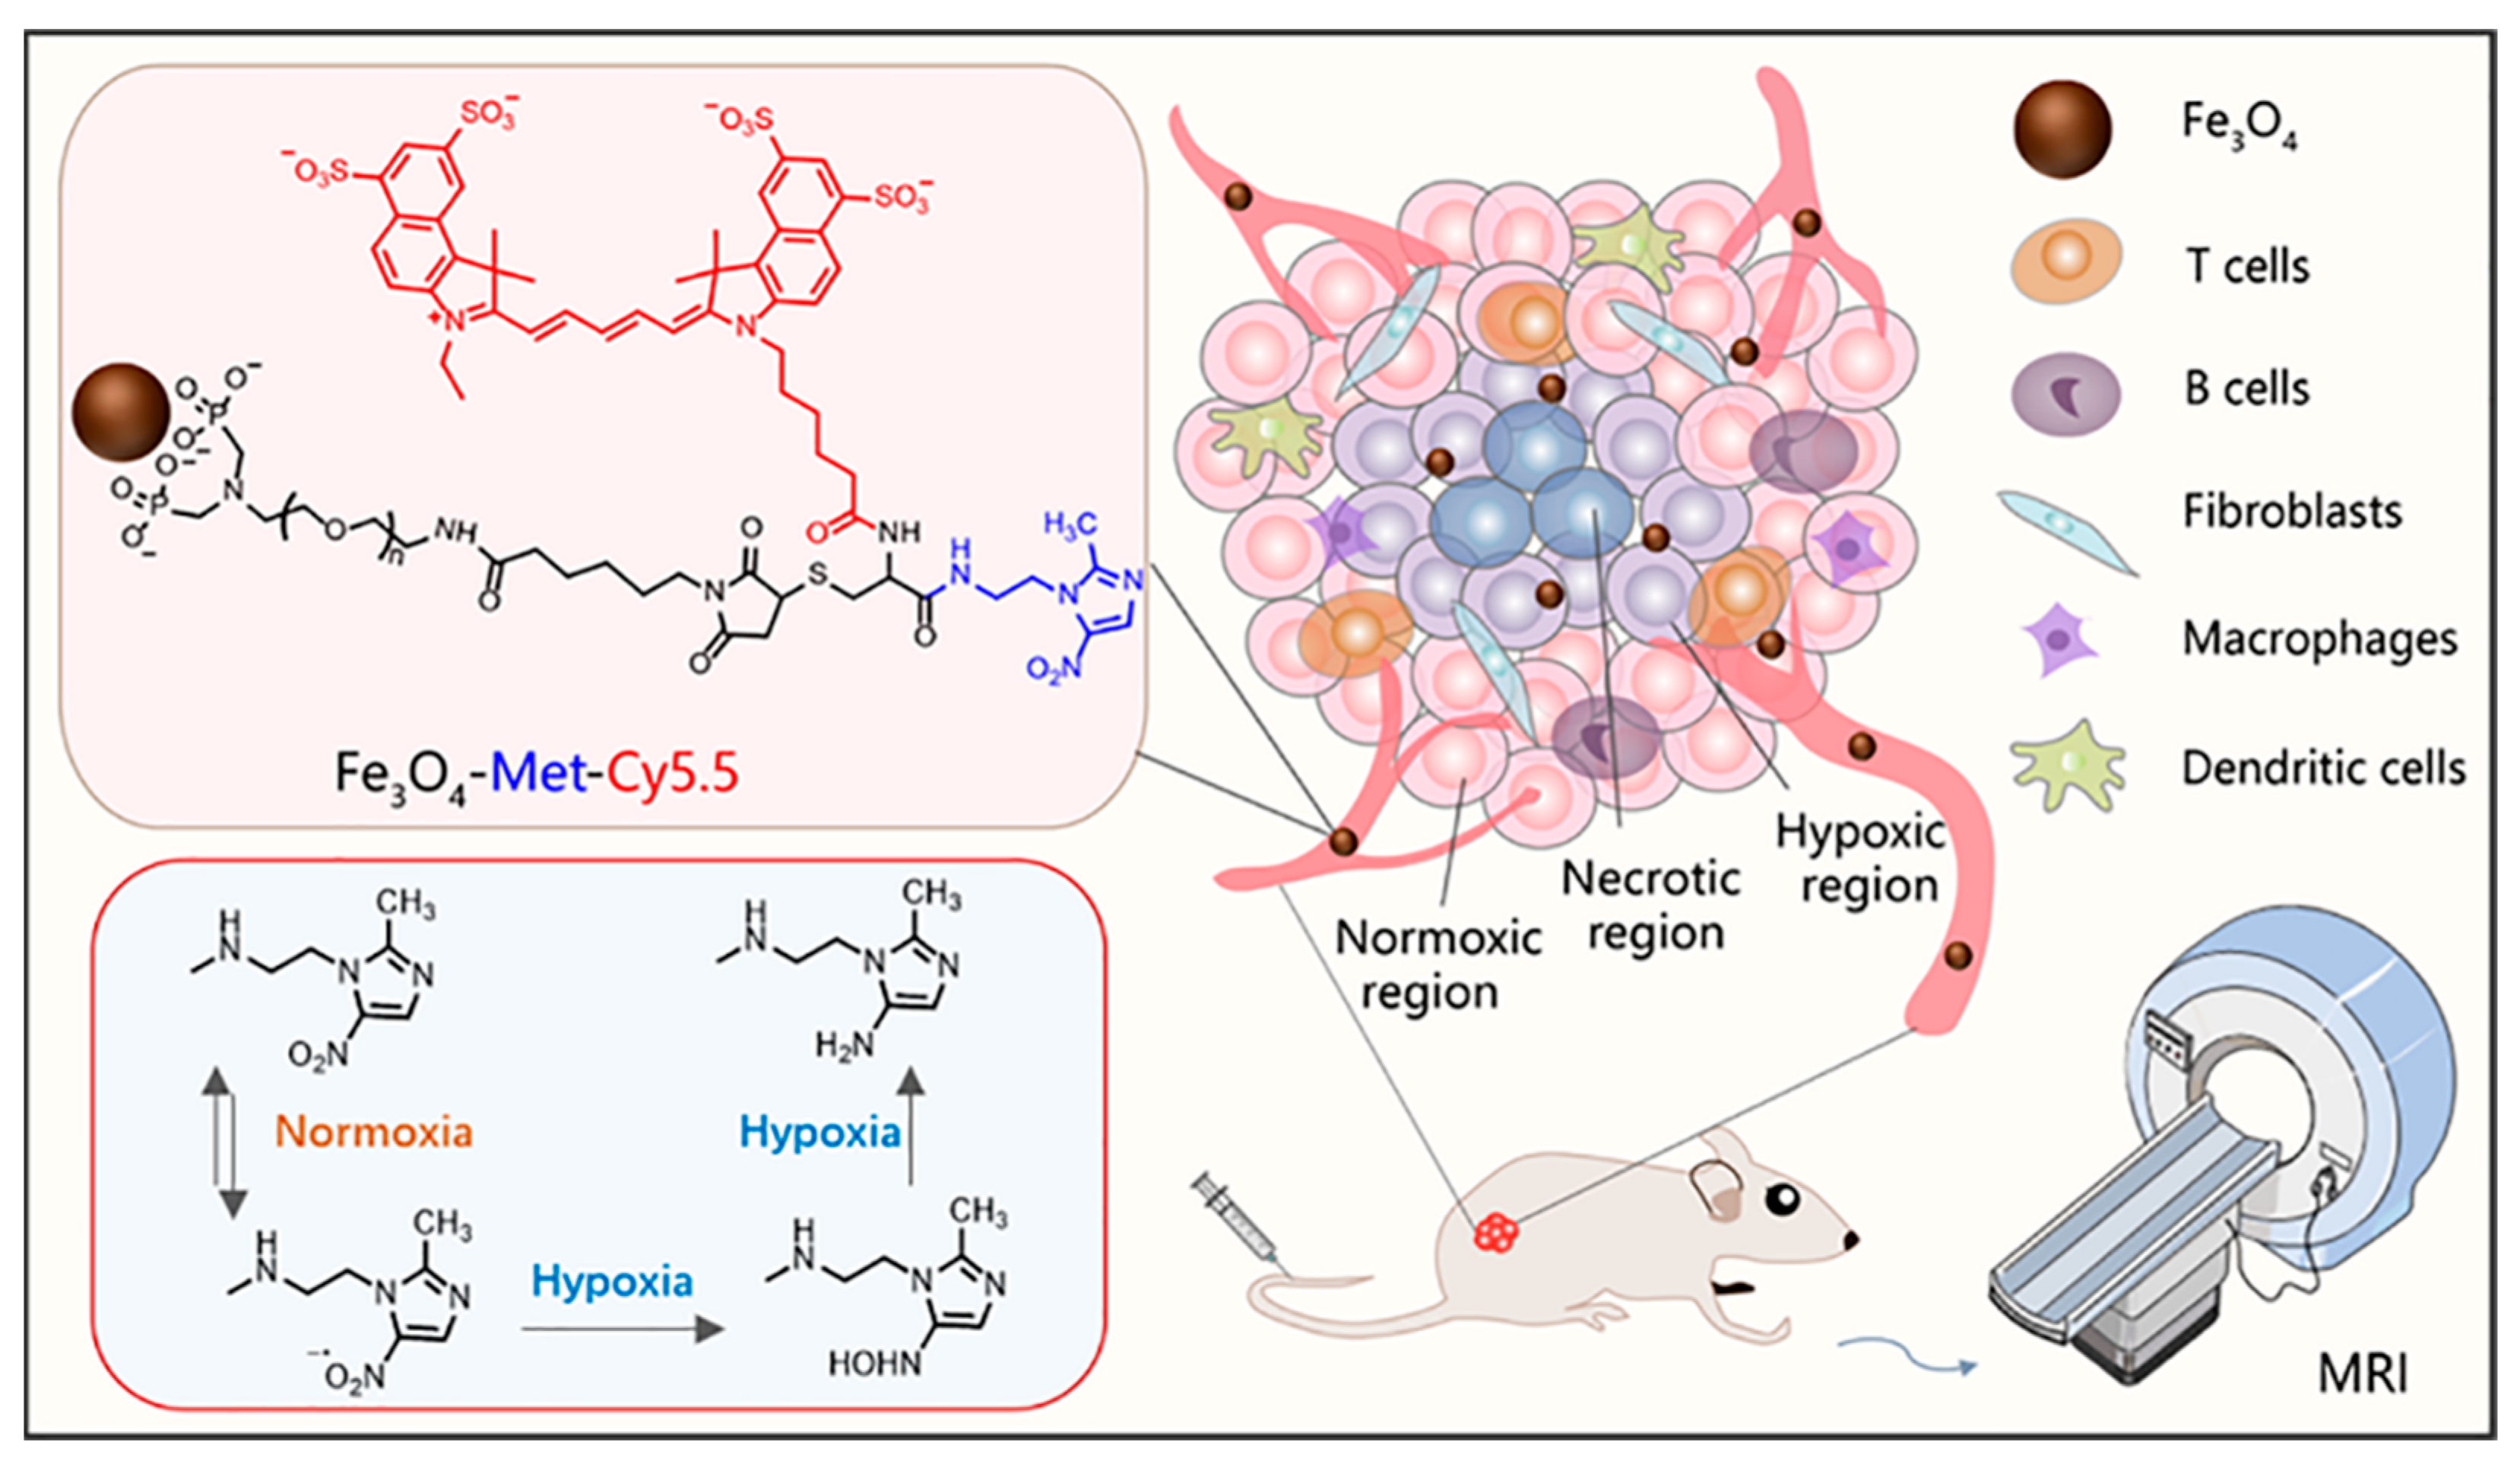

3.2. Construction and Characterization of Hypoxia-Sensitive MRI Nanoprobes